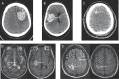

We demonstrate five consecutive cases of predominantly lobar COVID-19-associated intracerebral haemorrhage (ICH).